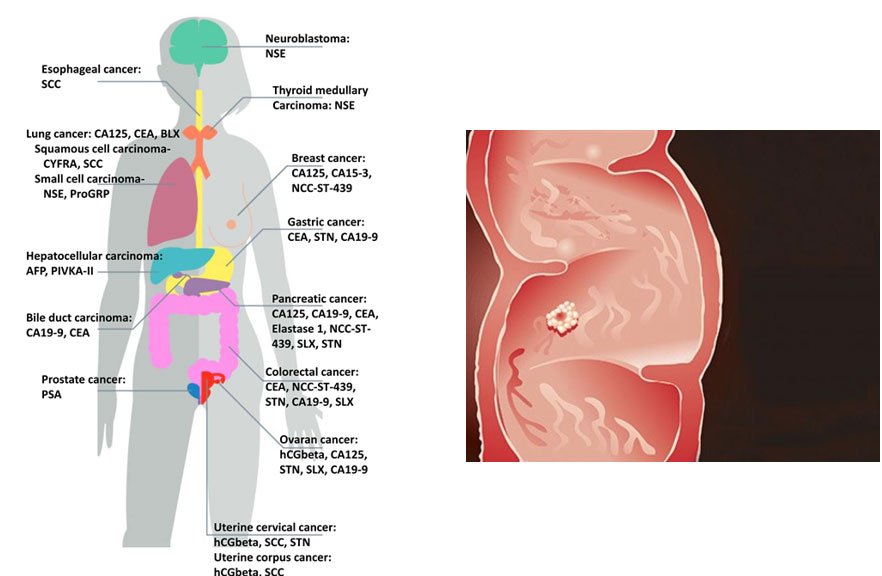

CA 242 یک نشانگر توموری مرتبط با آدنوکارسینوم و خطر متاستاتیک با واسطه e-selectin است. CA242 معمولاً همراه با CEA و CA19-9 برای تشخیص سرطان پانکراس آزمایش می شود. ویژگی CA 242 بیشتر از نشانگرهای مشابه است. تحقیقات کنونی حاکی از آن است که کارایی تشخیصی زمانی بالاتر است که نشانگرهای تومور مختلف به طور همزمان آزمایش شوند.CA 242 از نظر بالینی به عنوان یک نشانگر زیستی تشخیصی برای سرطان های پانکراس، کولورکتال و سایر سرطان ها استفاده شده است. از آنجایی که CA 242 در تومورهای بدخیم بیش از حد بیان می شود، منطقی است که فرض کنیم CA 242 می تواند محصول سلول های سرطانی باشد. مطالعه ای انجام شد که در آن سطوح سرمی CA 242 از 34680 بیمار با 27 بیماری بالینی تعریف شده به دست آمد. داده های به دست آمده نشان می دهد که بیماران مبتلا به سرطان لوزالمعده، سرطان دهانه رحم و لنفوم دارای بالاترین سطح سرم CA 242 بودند که پس از آن سرطان مری، روده بزرگ و تخمدان قرار داشت. همانطور که نشان داده شده است، می توان CA 242 را برای تشخیص سایر انواع سرطان نشان داد.